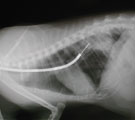

雑種猫、オス、21歳。体重3.55kg。慢性間質性肺炎の治療を3年間続けてきたが2ヶ月前より新たに左肺後葉背側部に浸潤影が現れ次第に呼吸状態が悪化してきたので気管支鏡検査を行うことになった。

びまん性網状影に加え後葉中央に浸潤影出現 2ヵ月後の入院時。呼吸が荒く食欲元気なし。 LB2D2より気管支鏡にて経気管支生検 検査後2日目元気になり退院。

経過:3年前呼吸荒いとのことで受診あり、浅速呼吸と胸部レントゲンでのびまん性間質影から慢性間質性肺炎と診断しステロイド治療を続けてきた。しかし嘔吐を機会に呼吸困難が起こったので来院した。努力性呼吸あり血液ガス分析にて低酸素血症(PaO2 69.1mm Hg)を示した。胸部レントゲンではびまん性網状影に加え左後葉中央部に浸潤影が出現していた。感染の可能性ありステロイドを中断し気管支拡張と抗生剤療法に切り替えた。2ヶ月後、呼吸状態は悪化し低酸素血症も進行した(PaO2 51.9mm Hg)。慢性間質性肺炎の再燃の可能性あり、浸潤影の原因解明のため気管支鏡にて気道の観察と浸潤影領域の生検を施行した。気道粘膜全体には異常がみられなかった。生検は透視下にてLB2D2に慎重に鉗子を挿入し行った。3回繰り返した。白色粘液状物が採取されたが細菌・真菌は検出されず、細胞診ではわずかの炎症細胞と気管粘膜上皮のみで腫瘍性変化はみられなかった。浸潤影は粘液栓によるもので、呼吸状態悪化はステロイド中断による間質性肺炎の再燃と考えられた。検査後、粘液栓を取り除いたためか全身状態は良好となり2日目に退院となった。その後、ステロイドと去痰剤投与を始め元気食欲が極めて改善した。